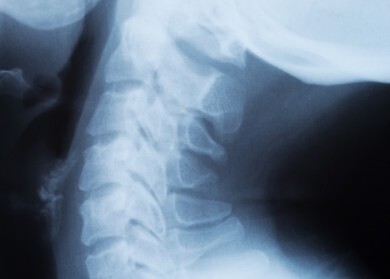

Another type of neck pain is cervical herniated disc. When the inside portion of the disc, as well as the cervical disc itself, has a tear, this may herniate to the annulus or the outer part. Then, the nerve root may become pinched, and this can result to pain that is felt into the hands and along the arms.